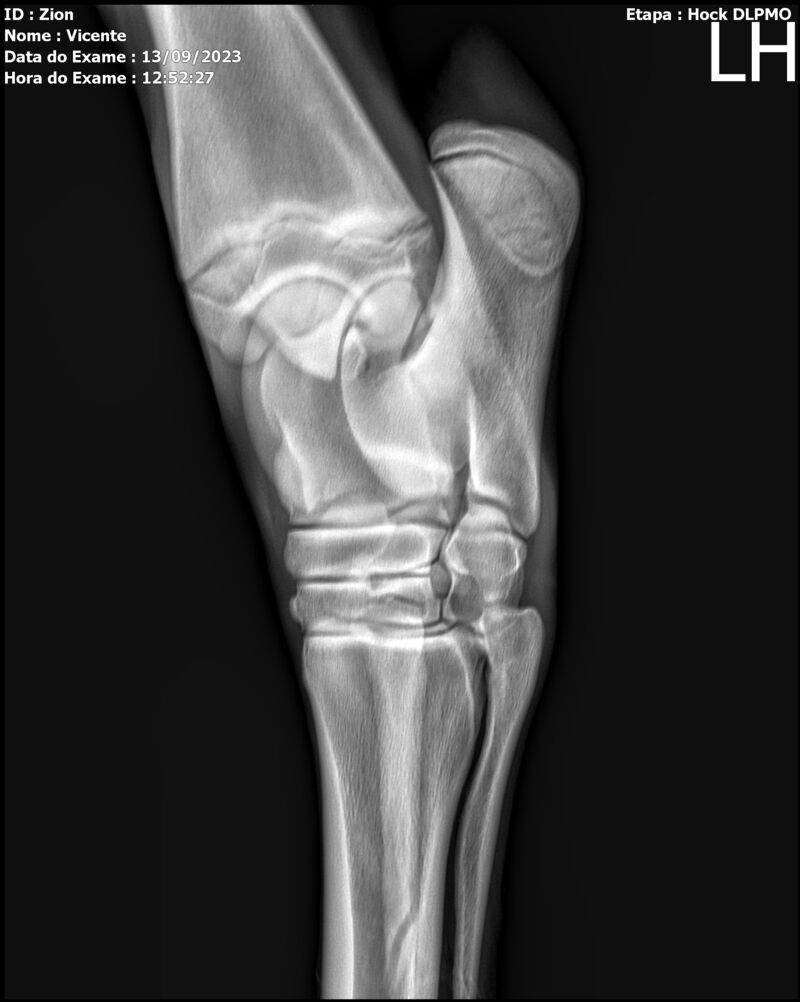

ZION ZC

Raça: BRASILEIRO DE HIPISMO

Sexo: MACHO - POTRO

Nascimento: 17/12/2022

Altura Aproximada: 1,51

Pel.: CASTANHO

Registro: EM AND

Vend.: VICENTE CONTE

Local : PORTO FELIZ/SP